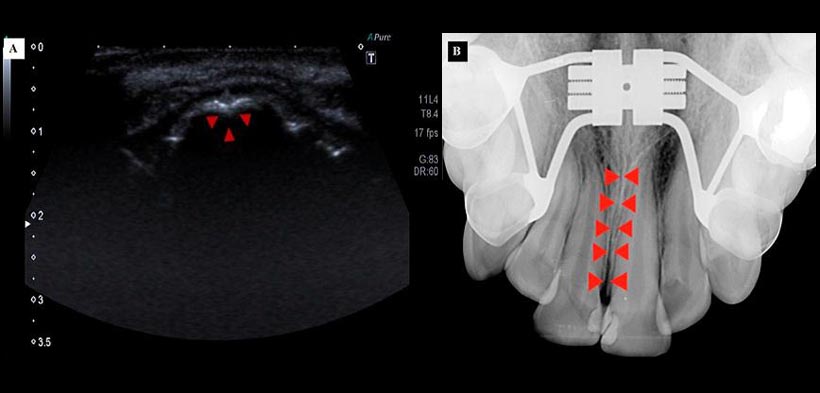

Figura 3. (A) Ecografía del maxilar superior antes de la expansión, casi no se observa la sutura palatina (puntas de las flechas). (B) Radiografía oclusal del maxilar superior, antes de la expansión de la sutura palatina (puntas de las flechas).